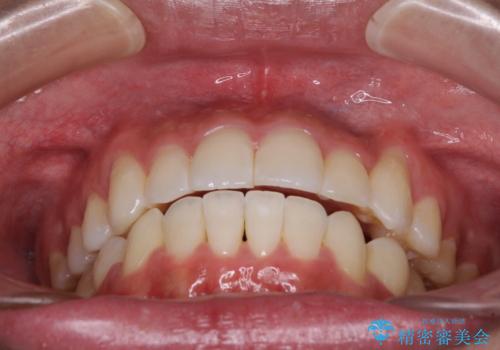

八重歯と奥歯のクロスバイト 上顎骨を拡大してインビザラインで矯正

- 八重歯を気にして来院された患者様です。

八重歯が著しいため、抜歯矯正も視野に入れて検討しましたが、臼歯の咬合関係は正常に近かったので、非抜歯矯正で進める方針としました。

上顎骨の幅が狭く、奥歯がクロスバイトとなっていたため、急速拡大装置を用いて上顎骨を側方拡大し、八重歯を収めるスペースを獲得しつつクロスバイトを改善することとしました。

上顎骨を思い通りに拡大できたため、当初の計画通りに非抜歯矯正で仕上げることができました。